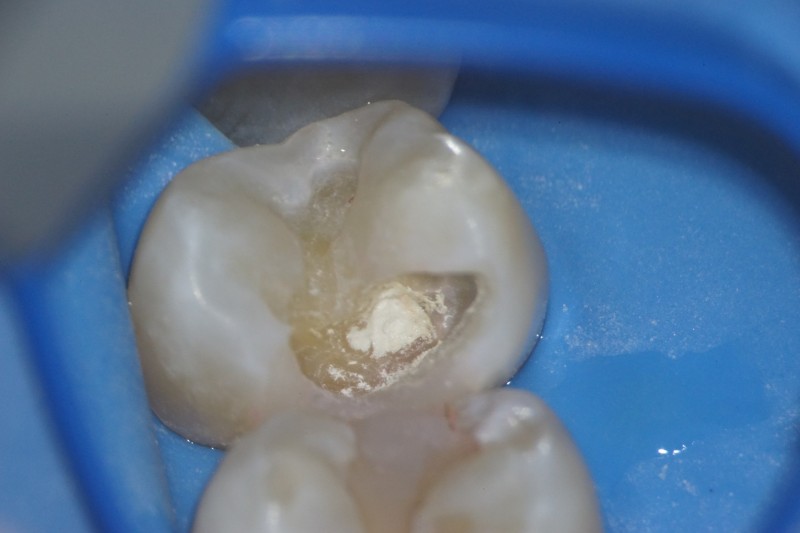

う蝕検知液で残っている虫歯を確認します。

歯肉側に、隔壁を作ります。

虫歯を除去すると、神経が露出しました。

神経を保護するセメントを詰めます。